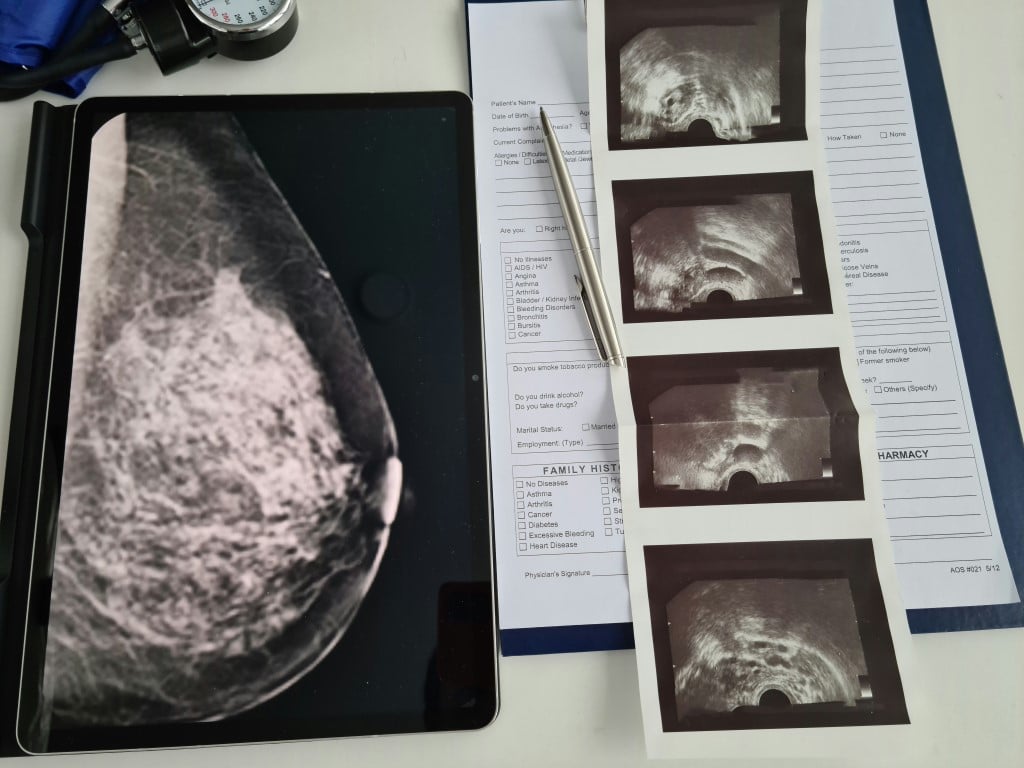

GETTING STARTED – UNDERSTANDING BREAST CANCER: A SIMPLE GUIDE

Breast cancer happens when cells in the breast grow in a way that isn’t normal. These cells can form a lump (called a tumour), and in some cases, may spread to other parts of the body. Not all lumps are cancerous – but when they are, your doctor will work with you to find the best way to treat them.

Doctor, senior woman and tablet for x ray results, lungs assessment and medical exam at hospital. Radiologist, elderly patient and online for chest scan, diagnosis and advice for healthcare treatment

AdobeStock_671817987